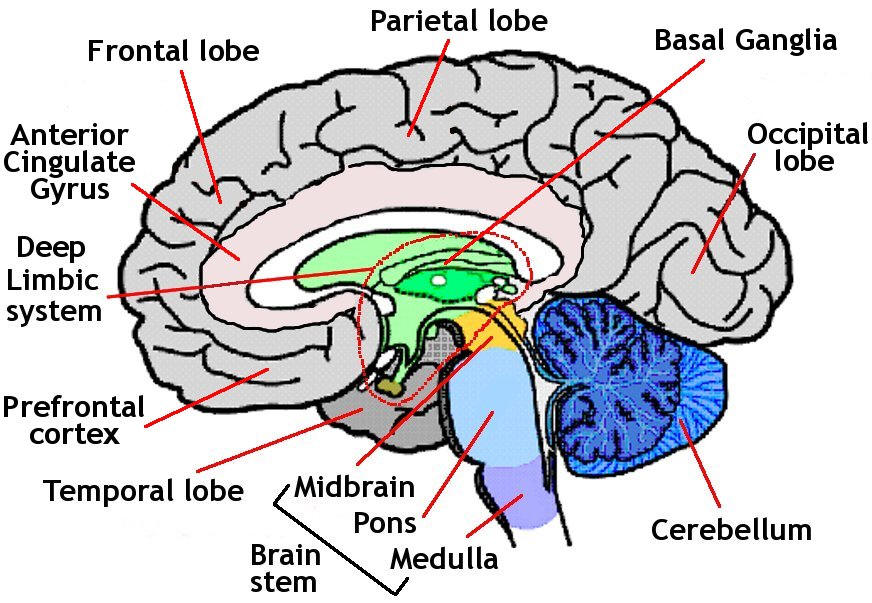

BASIC BRAIN ANATOMY

CEREBRUM

L2 HEMISPHERES

L4 LOBES: FRONTAL PARIETAL TEMPORAL OCCIPITAL

| FRONTAL LOBE | PARIETAL LOBE | TEMPORAL LOBE | OCCIPITAL LOBE |

|---|---|---|---|

| MOVEMENT | SENSORY INFO | HEARING | PROCESSING VISUAL INFO |

| PERSONALITY | PHYSICAL LOCATION | SMELL | |

| COUNTING | GUIDES MOVEMENT in 3D SP | MEMORY | |

| SPELLING | RECOGNITION of FACES | ||

| DECISION-MAKING |

SYMPTOMS VARY, DEPENDING on REGION of DAMAGE

FRONTAL LOBE → PERSONALITY CHANGE

PARIETAL LOBE → LOSS of SPEECH (APHASIA)

TEMPORAL LOBE→ DIFFCULTY with MEMORY